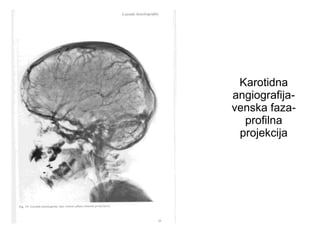

Karotidna

angiografija-

venska faza-

profilna

projekcija